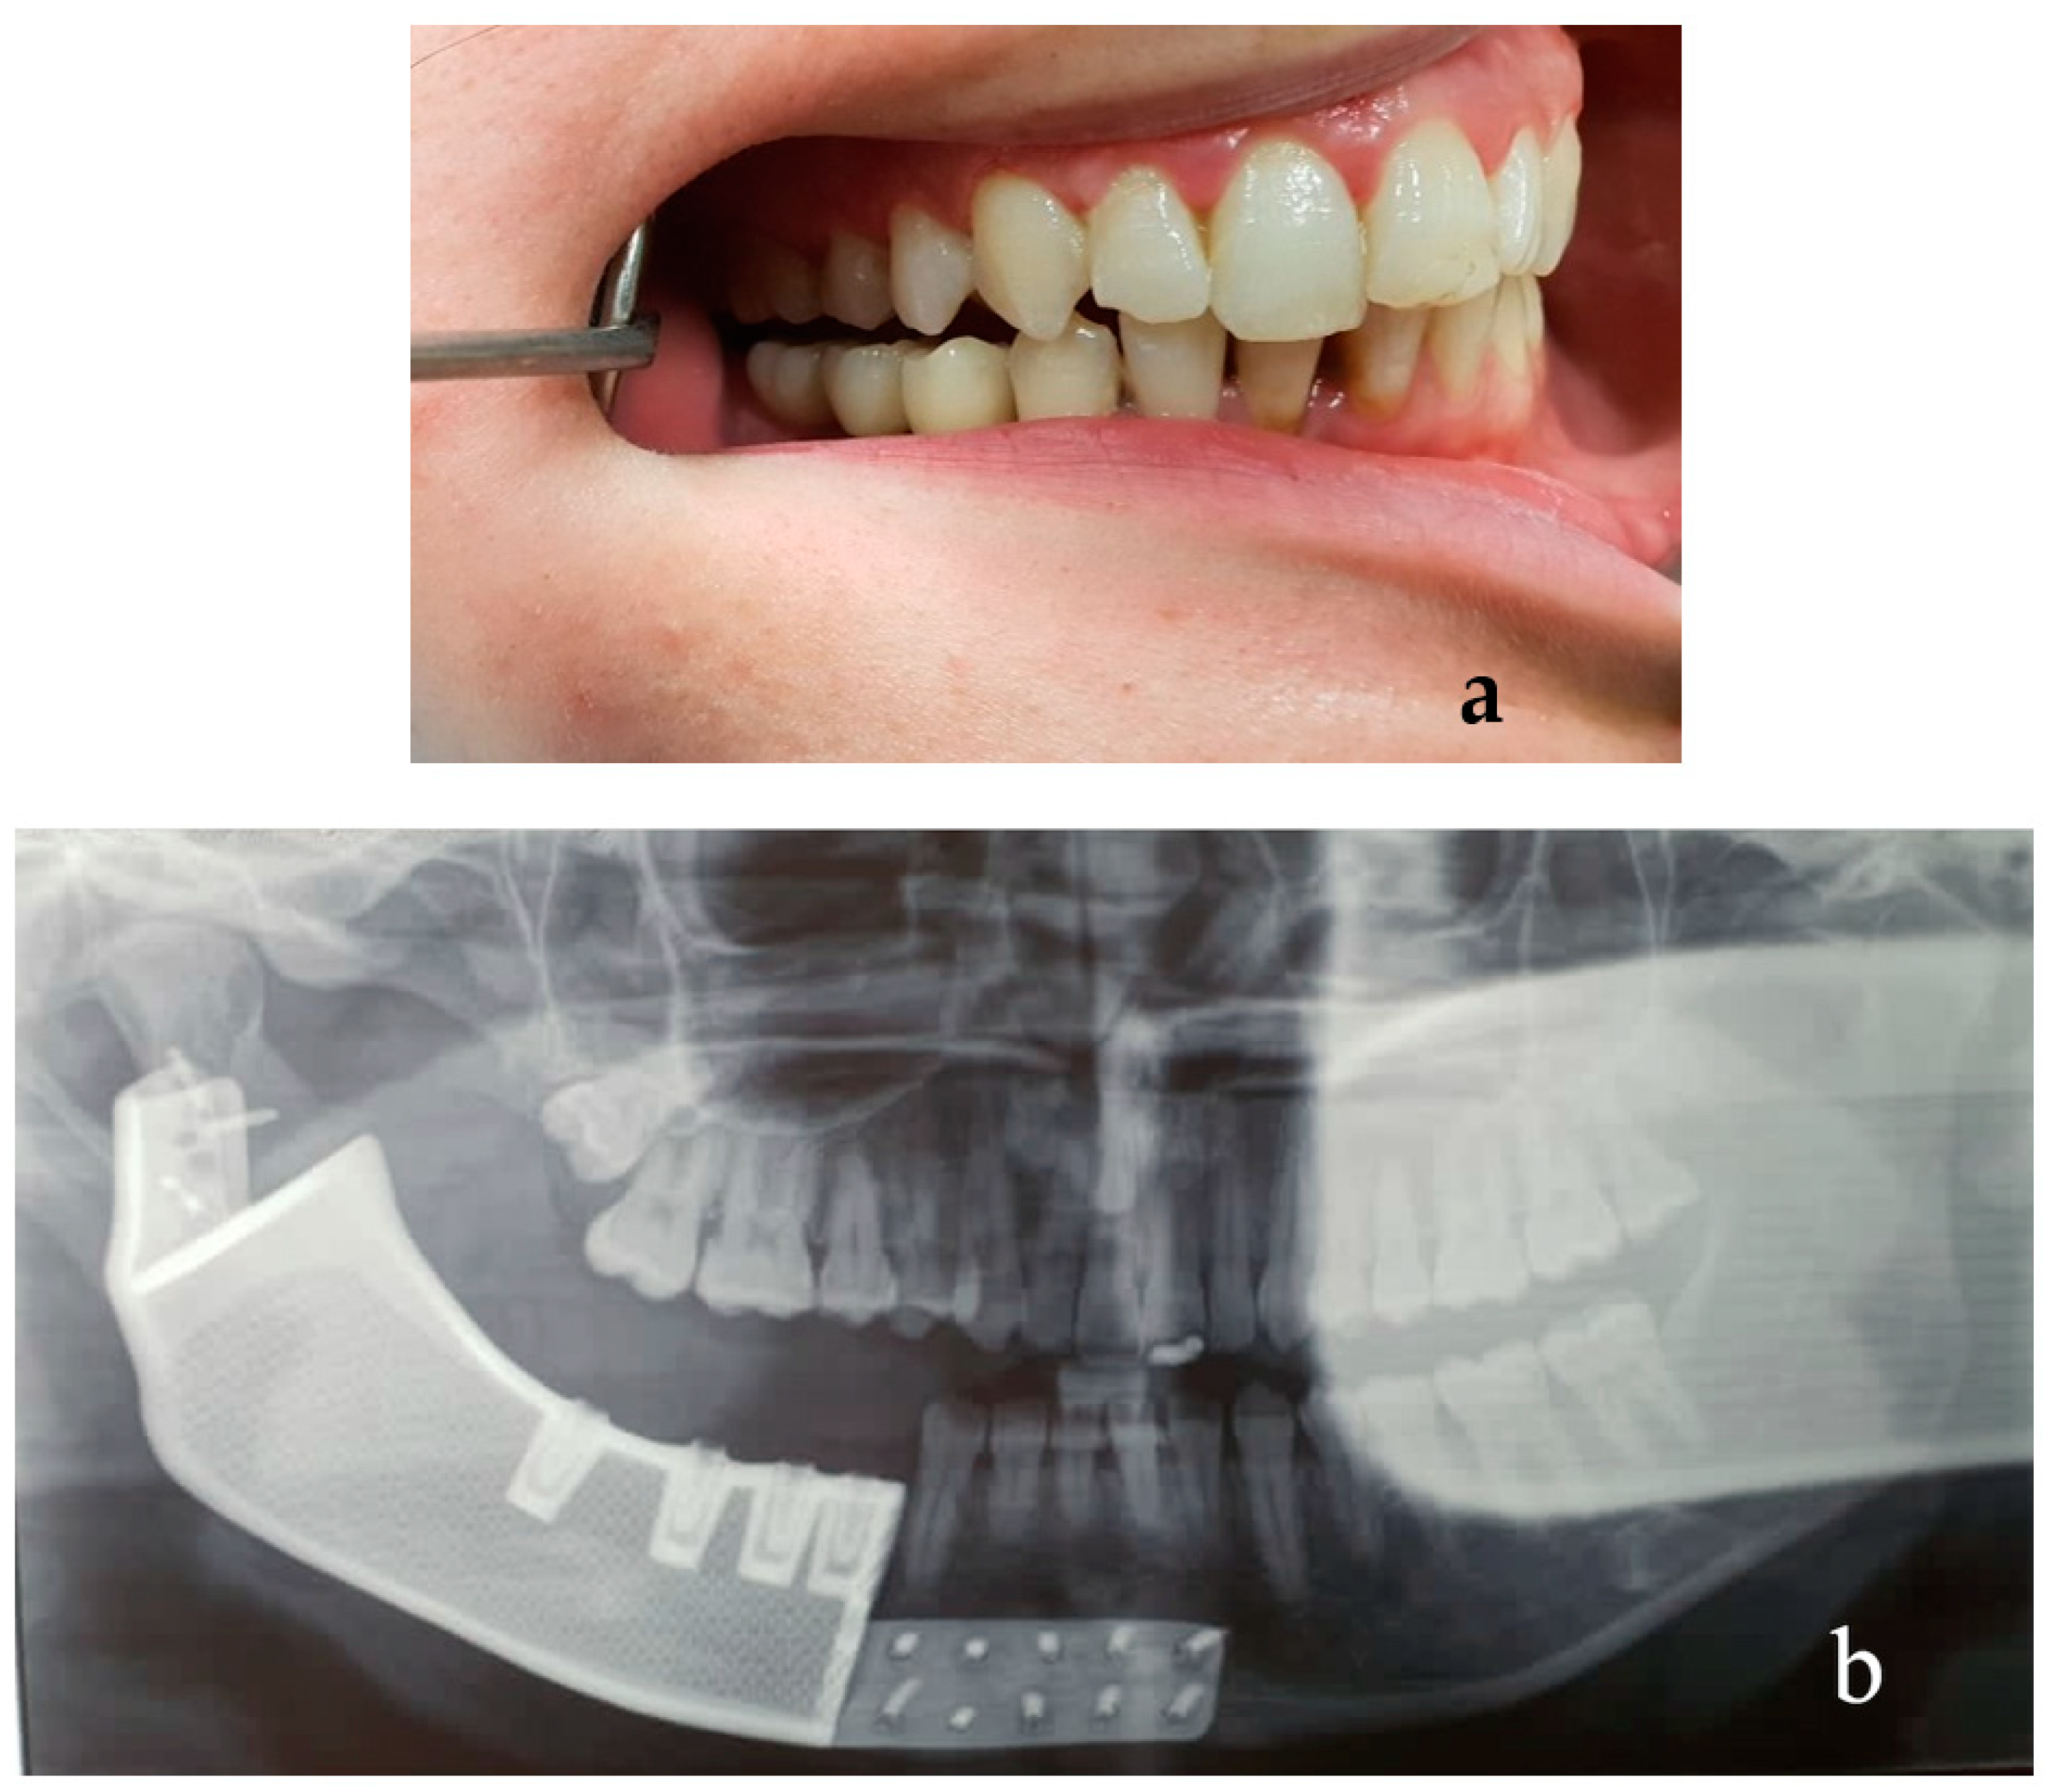

2.5. Results Case #1

2.6. Patient #2

2.9. Results Case #2

3. Discussion